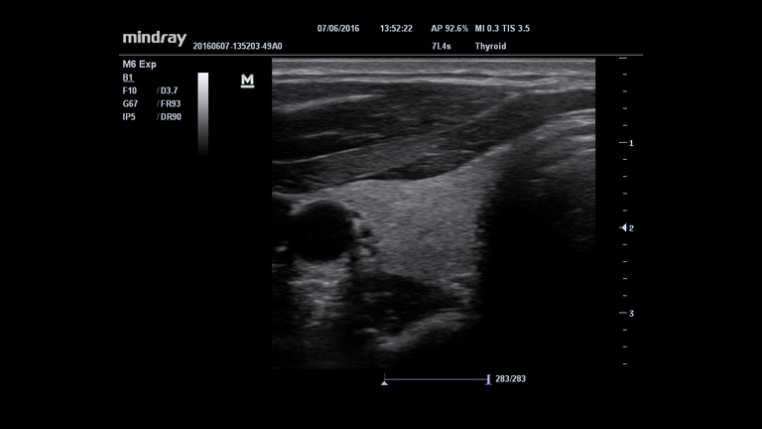

- 7L4s

iNeedle™

Doskonałe narzędzie do wykonania biopsji: pozwala na dopasowanie kąta linii skanowania w celu uzyskania lepszej widoczności igły, nerwów i drobnych naczyń krwionośnych.